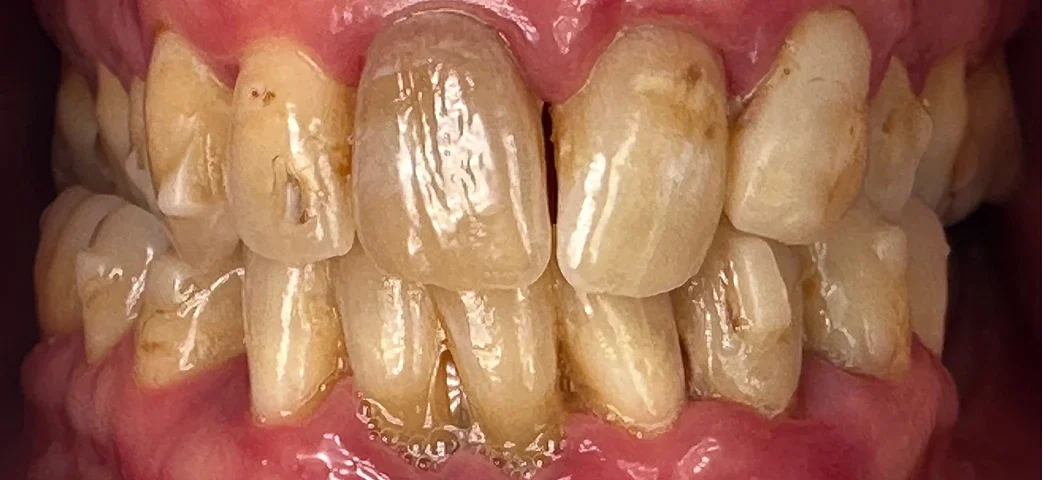

Our patient, a 41-year-old female from Portland, came to us in 2023 seeking help for what she described as "ugly teeth that don't work." She was unhappy with the dark, yellow discoloration and severe crowding. Smiling was something she avoided. Eating was difficult. Her lower teeth were painful and mobile, bleeding easily when brushing or chewing. Dental anxiety and financial concerns prevented her from moving forward at first — but a year later, motivated and ready, she returned determined to change her life.

On examination:

Upper Arch

- Teeth were discolored, worn, crowded and decayed.

- Arch form was narrow with a missing upper lateral incisor.

- Bone support was better than the lower arch, making these teeth restorable.

Lower Arch

- Advanced periodontal disease with significant bone loss.

- Multiple teeth were mobile and symptomatic.

- Two impacted retained teeth added complexity.

- Only a small number of posterior teeth were technically restorable — not ideal for long-term function.

Given her goals and clinical condition, restoring just a few teeth wouldn’t provide the stability or esthetics she needed. Instead, we developed a comprehensive plan that combined conservation where possible and replacement where necessary.